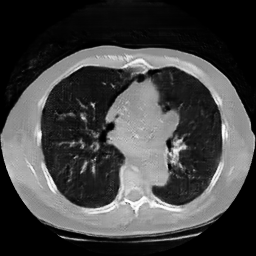

The study utilizes three 3D datasets, namely the GSP dataset[3], the LIDC-IDRI dataset[1], and the dataset employed for the Lung Nodule Analysis 2016 (LUNA16) challenge[21] which is a subset of LIDC-IDRI dataset. Samples from generated images at different stages of training are presented in Fig. 2 and Fig.3.

Refer to caption

20000

30000

40000

50000

60000

70000

80000

HA-GAN synthetic images at different iterations

Figure 3: Synthetic images of CRF-GAN and HA-GAN at different iterations of training on the LUNA16 dataset